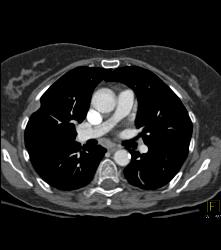

Lymphoma in Pleura and Ribs and Mesentery